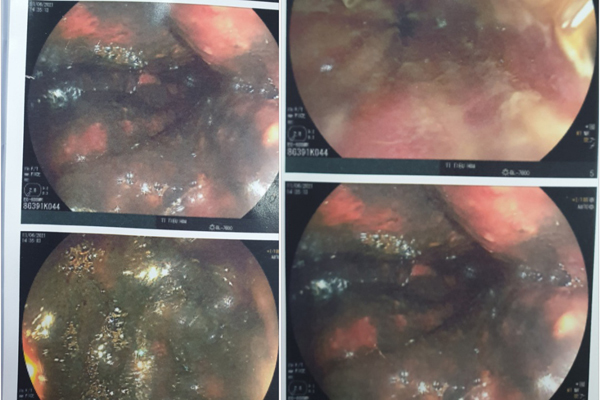

Đường tiêu hóa của bệnh nhân phù nề và xung huyết mạnh

Kết quả nội soi toàn bộ đường tiêu hóa cho thấy niêm mạc thực quản, dạ dày, tá tràng phù nề, xung huyết mạnh, dạ dày có nhiều dịch đen bẩn.